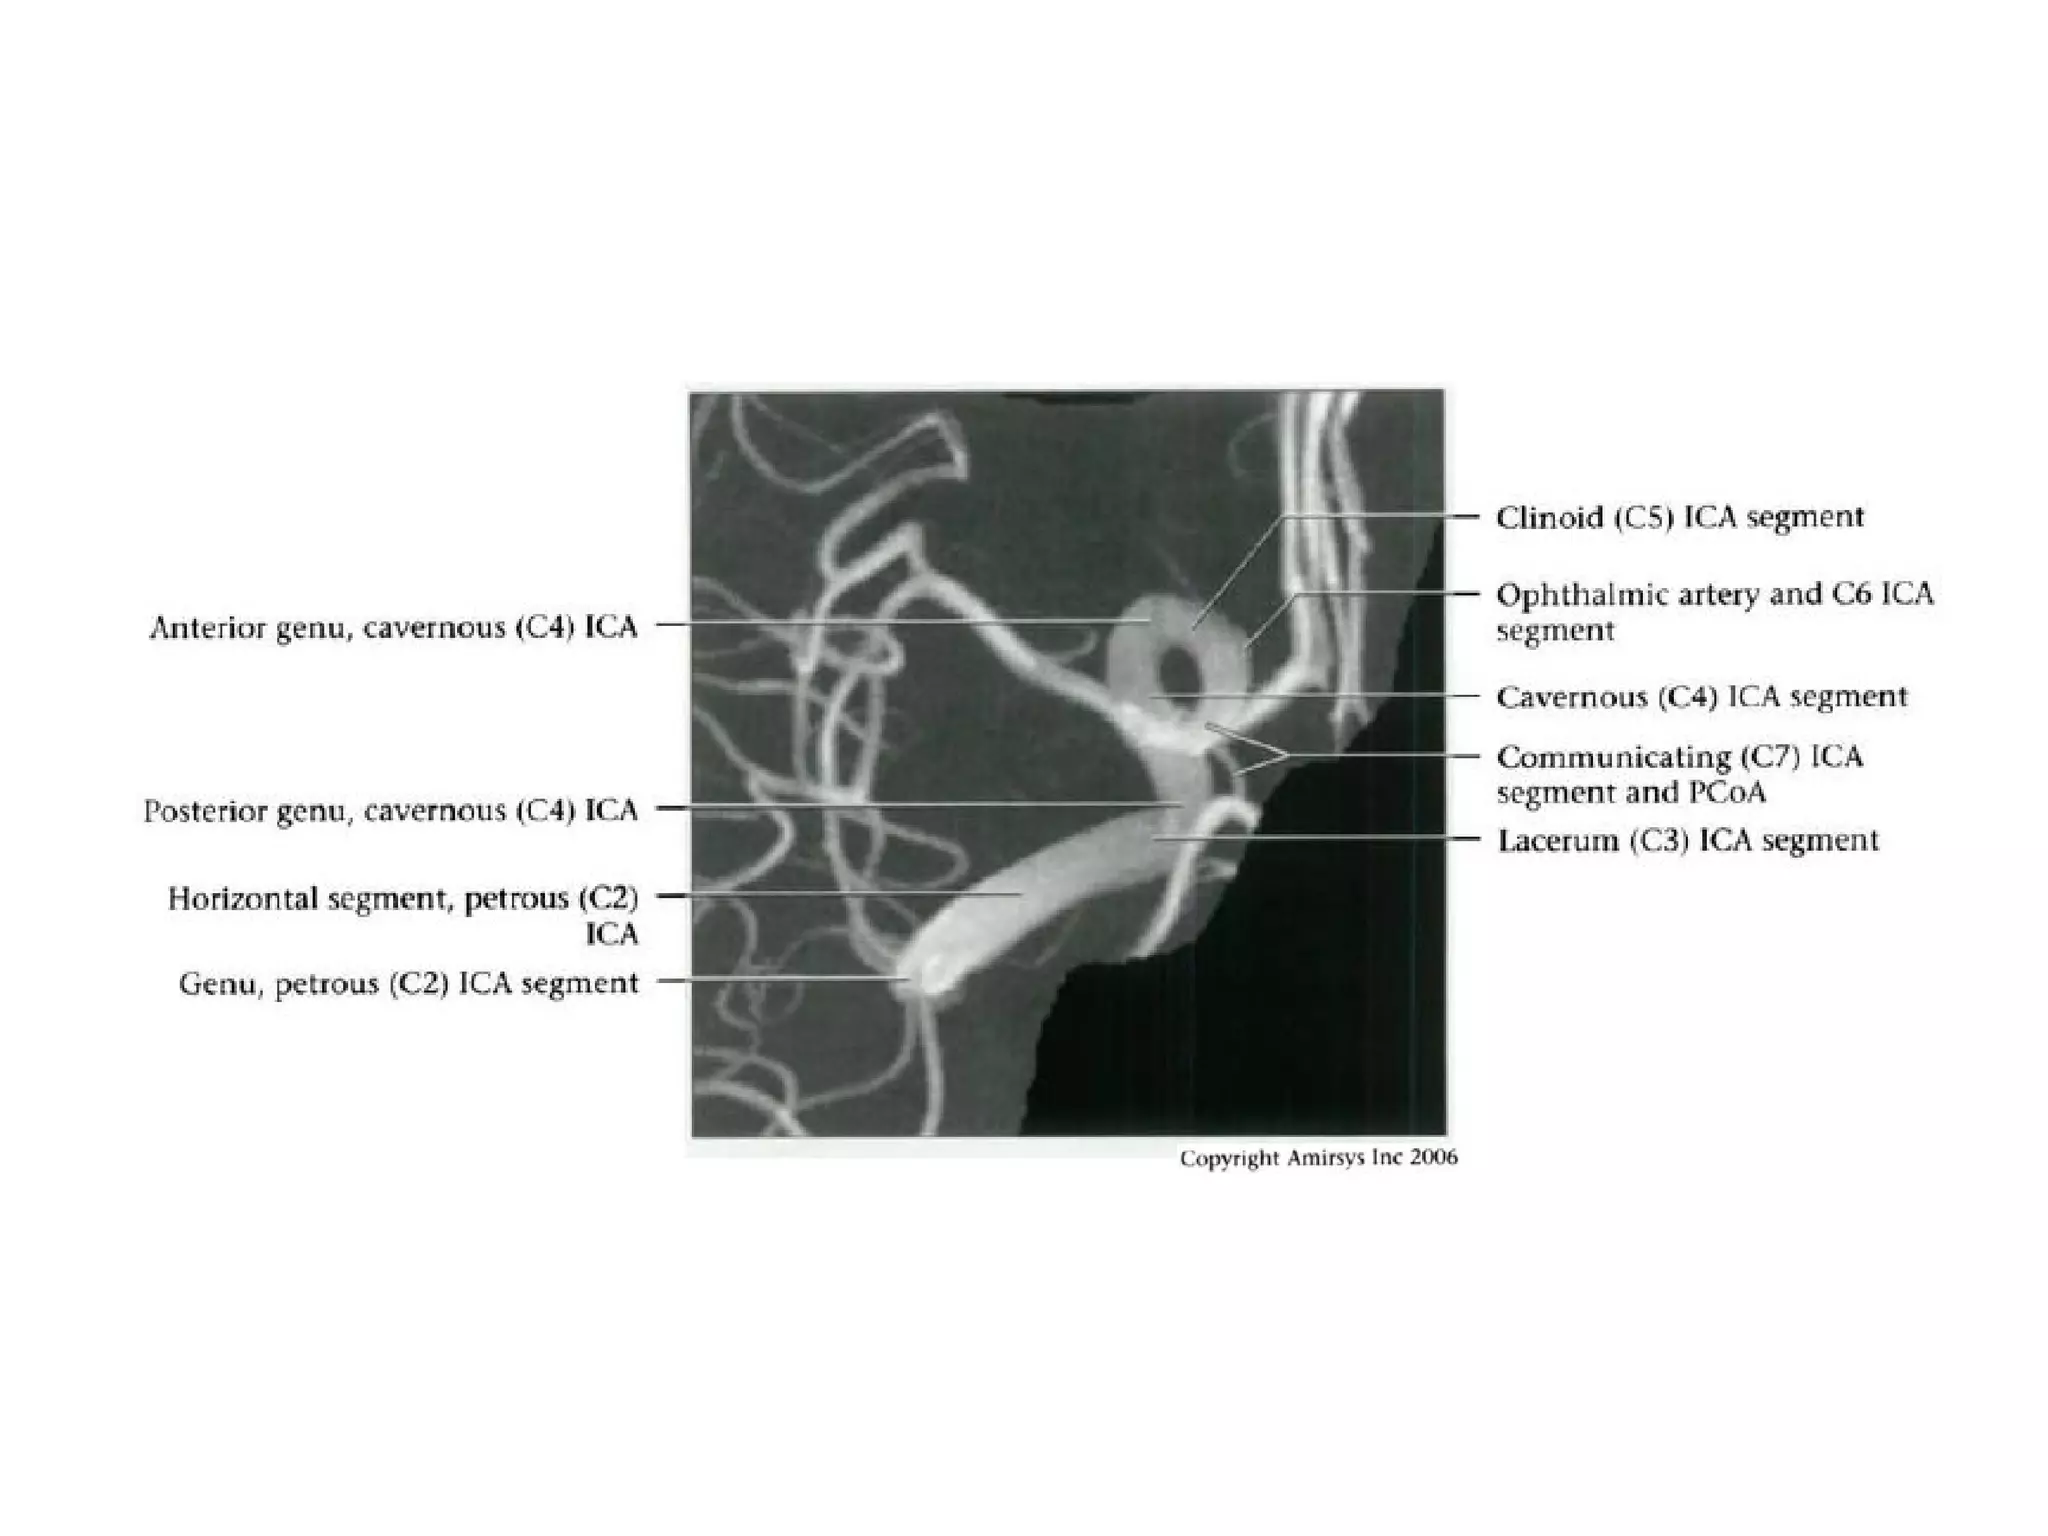

INTRACRANIAL INTERNAL

CAROTID ARTERY

Overview

• Complex course with several vertical /

horizontal segments, 3 genus (one

petrous, two cavernous)

• Six intracranial segments (Cervical lCA =

C1):

- Petrous (C2), Lacerum (C3),

Cavernous (C4), Clinoid (C5),

Ophthalmic (C6), Communicating (C7)

Petrous (C2) segment

• Contained within carotid canal of temporal bone

- Surrounded by extensive sympathetic plexus

- Two C2 subsegments joined at genu

• Short vertical segment - anterior to internal jugular vein

(lJV)

• "Genu" (where petrous ICA turns anteromedially in front

of cochlea)

• Longer horizontal segment

- Exits carotid canal at petrous apex

- Branches

• Vidian artery (artery of pterygoid canal)

anastomoses with external carotid artery (ECA)

• Caroticotympanic artery (supplies middle ear)

Lacerum (C3) segment

• Small segment that extends from petrous

apex above foramen lacerum, curving

upwards toward cavernous sinus

• Covered by trigeminal ganglion

• No branches

Cavernous (C4) segment

• Three subsegments joined by two genus (knees)

- Posterior vertical (ascending) portion

- Posterior (more medial) genu

- Horizontal segment

- Anterior (more lateral) genu

- Anterior vertical (subclinoid) segment

• Covered by trigeminal ganglion posteriorly

• Abducens nerve (CN6) is inferolateral

• Major branches

- Meningohypophyseal trunk (arises from posterior

genu, supplies pituitary, tentorium and clival dura)

- Inferolateral trunk arises from horizontal segment,

supplies cavernous sinus (CS) dura / cranial nerves;

anastomoses with ECA branches through foramens

rotundum, spinosum, ovale

Clinoid (C5) segment

• Between proximal, distal dural rings of

cavernous sinus

• Ends as ICA enters subarachnoid space

near anterior clinoid process

• No important branches unless ophthalmic

arteries arises within C5

Ophthalmic (C6) segment

• Extends from distal dural ring at superior clinoid

to just below posterior communicating artery

(PCoA) origin

• Two important branches

- Ophthalmic Arteries (originates from

anterosuperior ICA, passes through optic canal

to orbit; gives off ocular, lacrimal, muscular

branches; extensive anastomoses with ECA)

- Superior hypophyseal artery (courses

posteromedially; supplies anterior pituitary,

infundibulum, optic nerve / chiasm)

Communicating (C7) segment

• Extends from below PCoA to terminal lCA bifurcation

into anterior cerebral artery (ACA), middle cerebral artery

(MCA)

• Passes between optic (CN2), oculomotor (CN3) nerves

- Posterior communicating artery

- Anterior choroidal artery (courses posteromedial,

then turns superolateral in suprasellar cistern; enters

temporal horn at choroidal fissure; supplies choroid

plexus, medial temporal lobe, basal ganglia,

posteroinferior internal capsule)